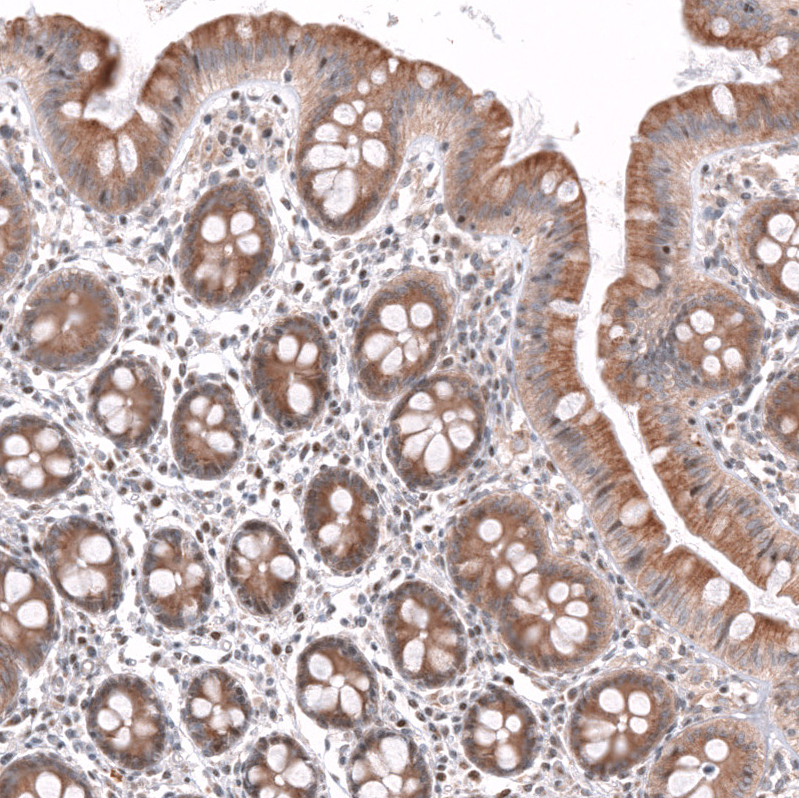

Immunohistochemical staining of human testis shows strong nuclear positivity in cells in seminiferous ducts.